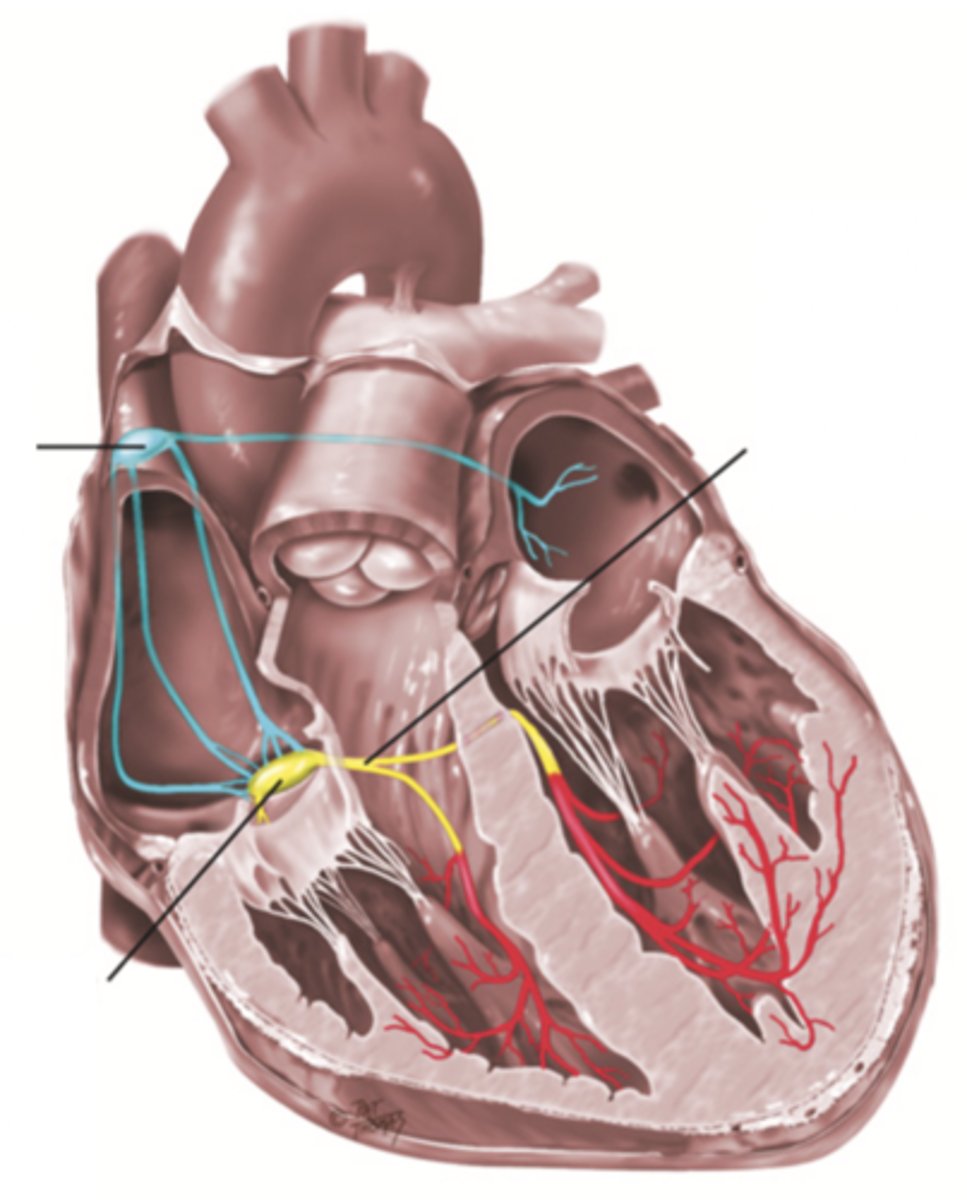

4 Parts of the Heart's Conduction System

- Sinoatrial (SA) node

- Atrioventricular (AV) node

- Bundle of His

- Purkinje fibers

Sinoatrial (SA) Node

Pacemaker of the heart conduction system, located at the right atrium (light blue)

Atrioventricular (AV) Node

The part that relays electrical impulses from atria into the bundle of his in the heart's conduction system; delayed slightly (yellow)

Bundle of His

Part of the heart's conduction system that transmits the cardiac impulse from the atrioventricular node to the purkinje fibers (red)

Purkinje Fibers

Fibers in the ventricles that transmit impulses to the right and left ventricles, causing them to contract